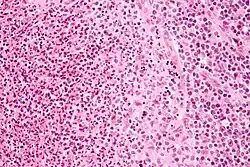

Cat-scratch disease is characterized by granulomatous inflammation on histological examination of the lymph nodes. Under the microscope, the skin lesion demonstrates a circumscribed focus of necrosis, surrounded by histiocytes, often accompanied by multinucleated giant cells, lymphocytes, and eosinophils. The regional lymph nodes demonstrate follicular hyperplasia with central stellate necrosis with neutrophils, surrounded by palisading histiocytes (suppurative granulomas) and sinuses packed with monocytoid B cells, usually without perifollicular and intrafollicular epithelioid cells. This pattern, although typical, is only present in a minority of cases.[16]